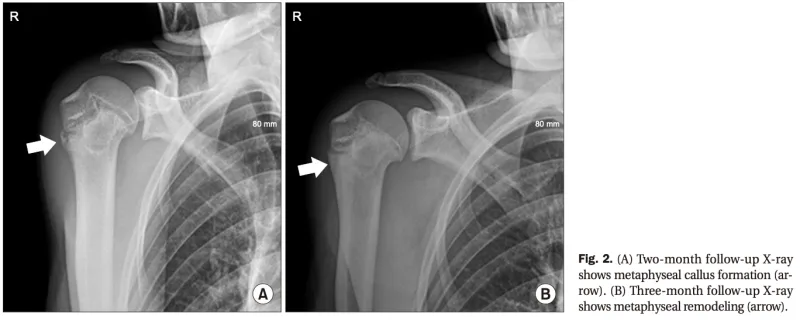

軟式テニス部の部長を務める活発な生徒さんで, 1カ月ほど前から右肩の痛みを訴えていたとのこと. 前医のX線写真では, 上腕骨近位部に骨膜反応が指摘され, 骨腫瘍の可能性が懸念されていました.

これは, 上腕骨の近位骨端線損傷に対する修復過程で認められます.

3ヶ月後のX線写真(B)では, 新しく作られた骨が成熟して, 普通の骨に変化しています.

引用元:Park JY. Little league shoulder: case reports. Arthrosc Orthop Sports Med. 2020. 7.

当院でX線およびCTを再撮像しましたが, 腫瘍性病変は認められませんでした.

成長軟骨(骨端線)の開大がみられ, 『リトルリーグ肩』(上腕骨近位骨端線損傷)と診断.

投球動作に似たサーブ練習の繰り返しによる, 成長期特有のスポーツ障害と判断しました.